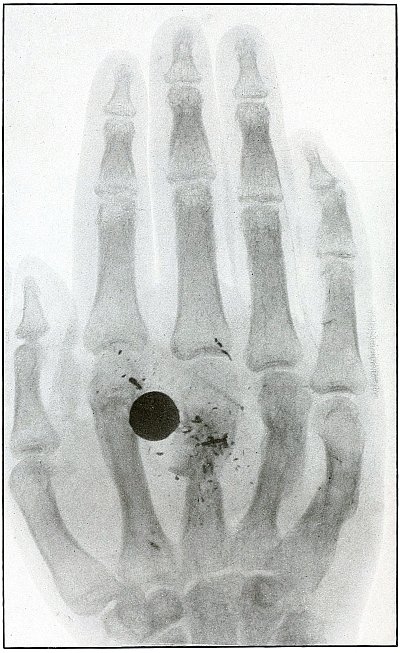

Plate 43.

[Pg 97]

Rifle—Plate 43.

UPPER EXTREMITY.

Gunshot Fracture of the Metacarpus.

Wound of entrance, inner aspect of the hand over proximal end of the

fifth metacarpal.

Wound of exit, on the outer border of the hand over the distal end of

the second metacarpal.

The velocity of the bullet was in mid or long range, as it displaced

no fragments, and as it made a point of entrance and exit about the

same in appearance.

The wound was infected, which is more frequently the case in the hand

than in the forearm.

The treatment is conservative with free incision and drainage

in the management of infection.

[Pg 98]